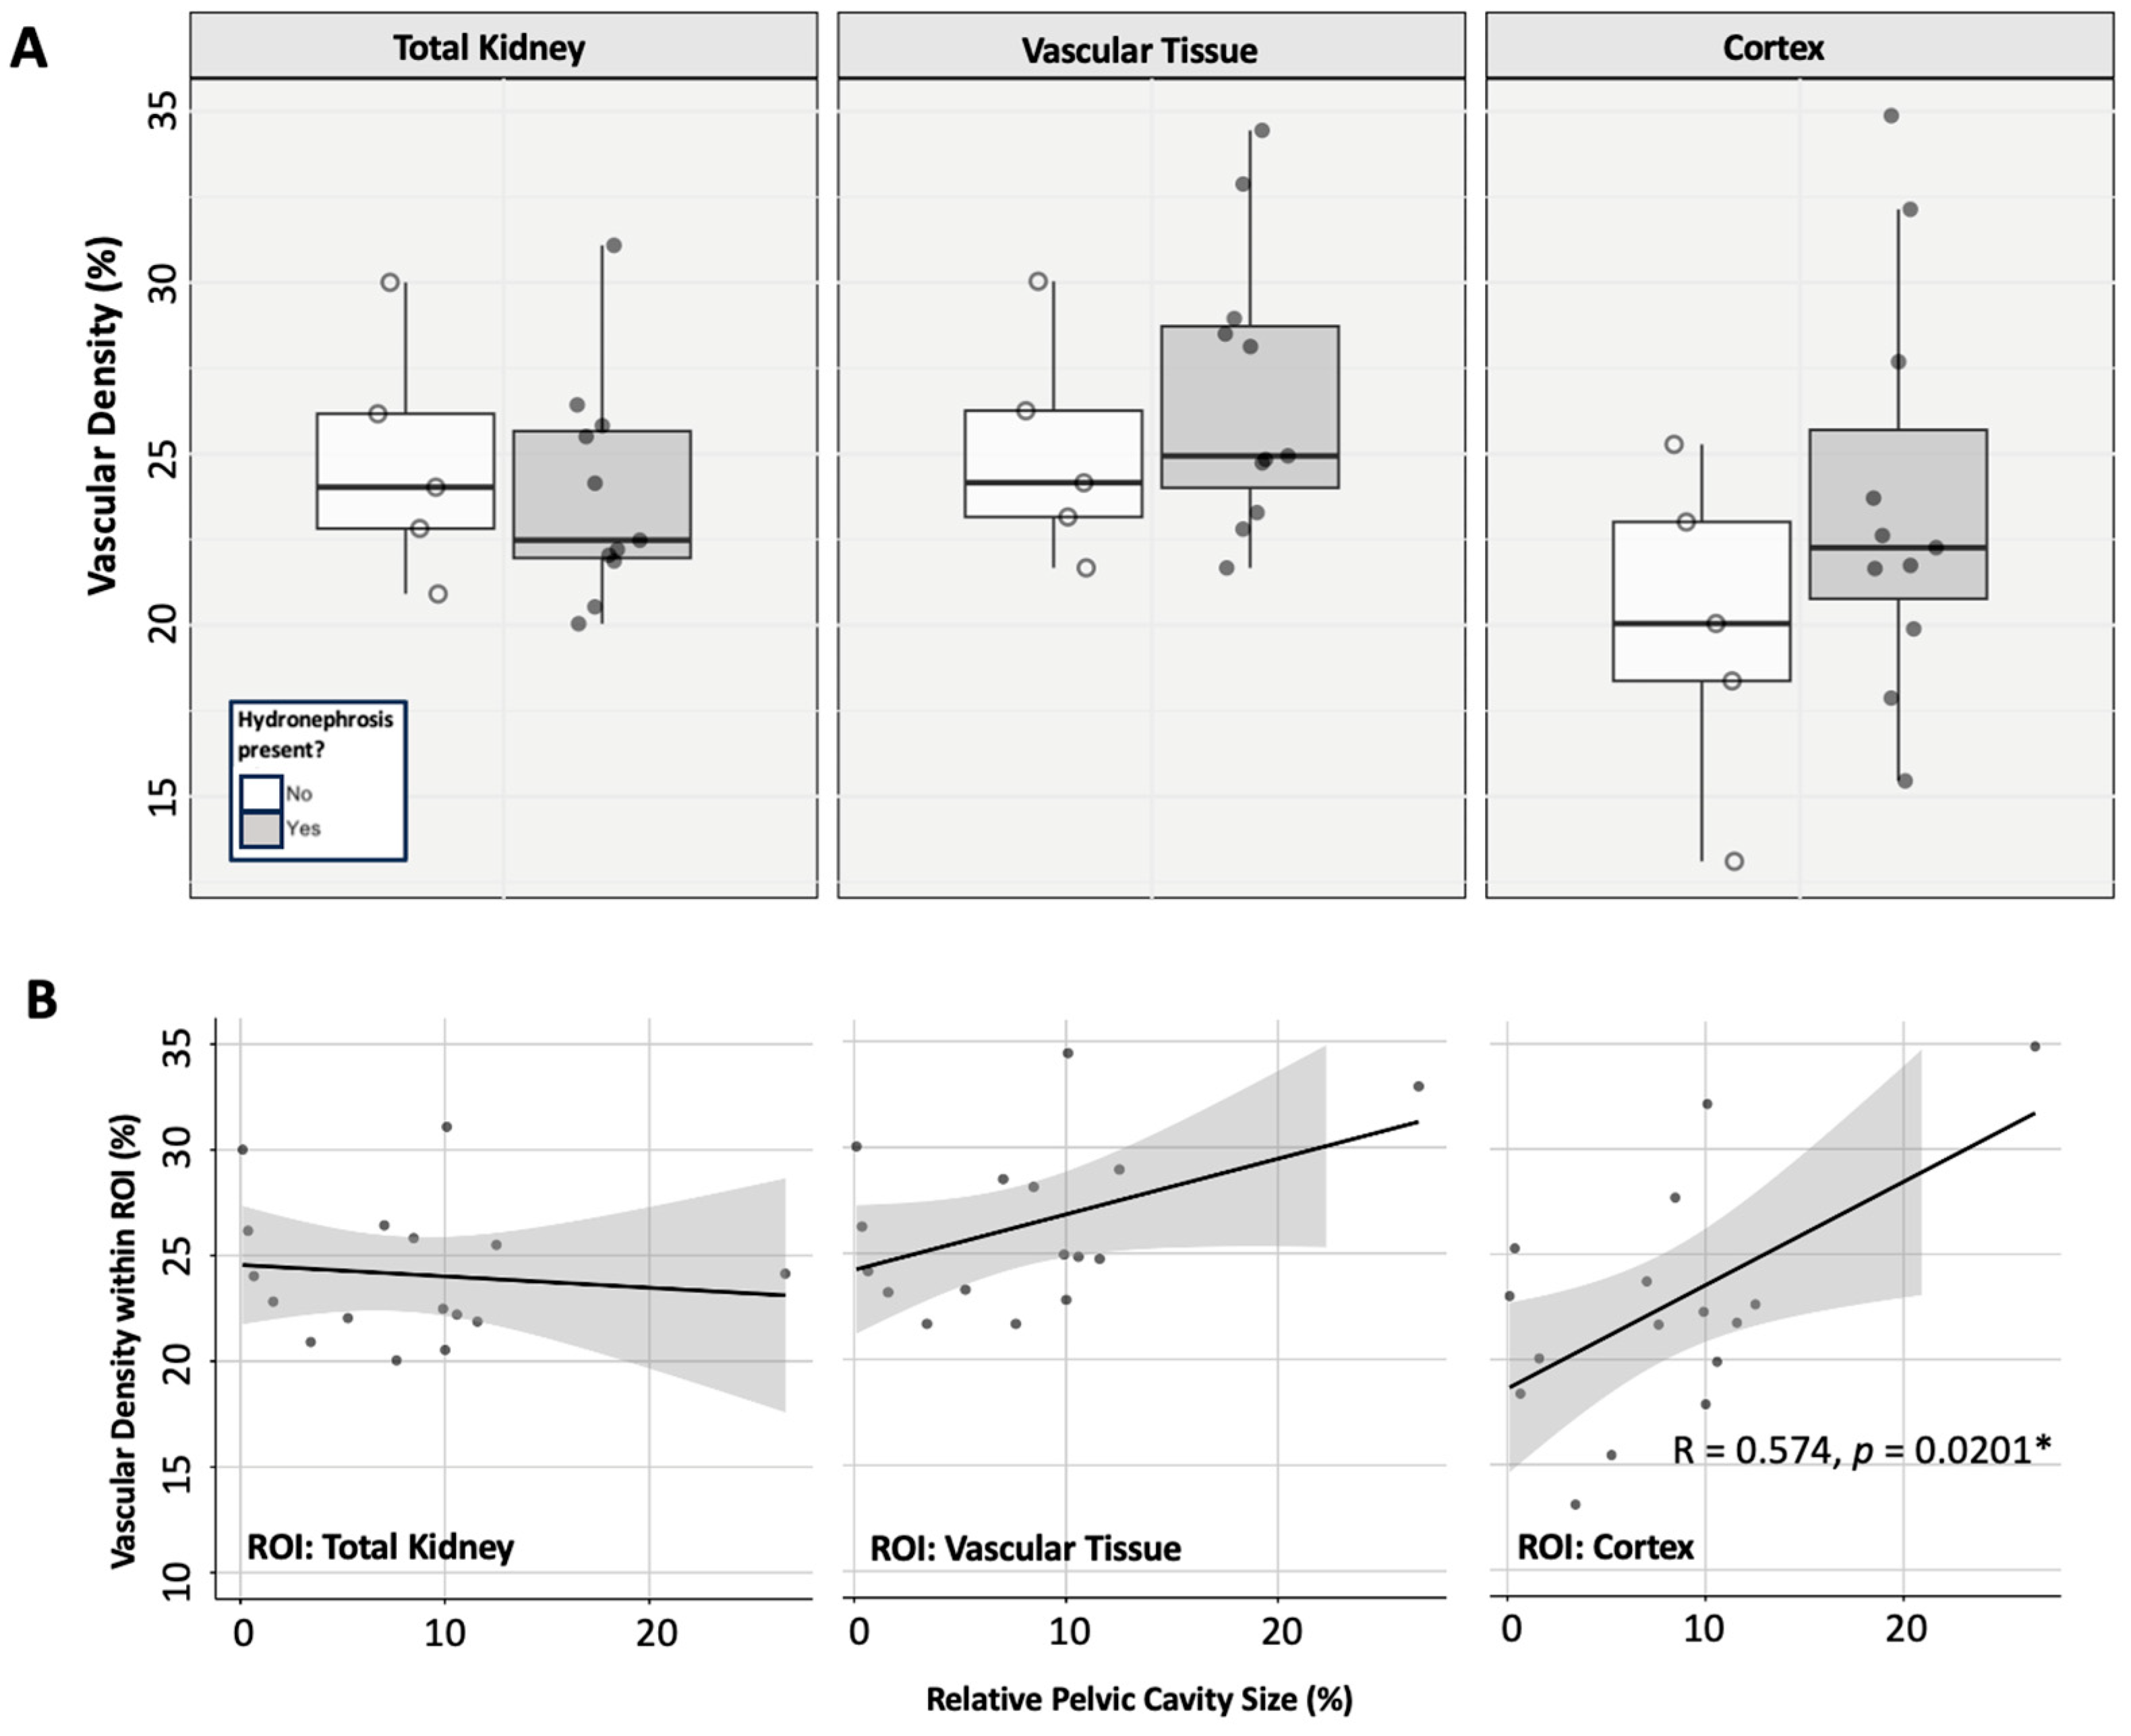

3.4.1. Renal Vascularity

3.4.2. Histological Tissue Architecture